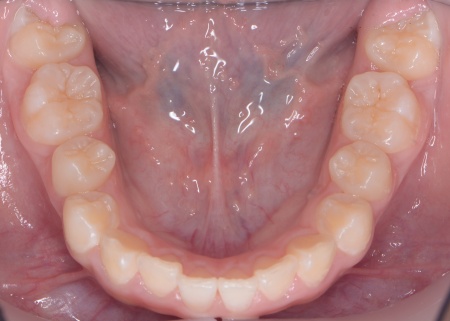

| カウンセリング | 拝見したところ、上の犬歯が歯列の外側に飛び出すように生えている、いわゆる八重歯でした。 さらに、上下の歯全体がデコボコに生えている「叢生(そうせい)」と呼ばれる状態で、これは歯が正しい位置に並ぶためのスペースが不足していることが原因だと考えられます。 このまま放置して顎の成長が完了してから矯正治療を行う場合、歯を並べるスペースを確保することが難しく、永久歯を抜く処置が必要になるケースがあります。 以上のことから、今の段階で歯並びを整える治療が必要だと診断しました。 |

患者様のご家族は「将来的な抜歯はできるだけ避けたいので、今のうちに治療をしたい」と希望されたため、成長期の段階で歯列を広げ、歯が並ぶスペースを確保する小児期の矯正治療「1期矯正」を提案しました。

メリット デメリット また、治療にあたりお口全体のバランスを確認したところ口元の突出はなく、顎のサイズはやや小さめですが、成長期であることから歯列の拡大が可能な状態だと判断しています。 以上の内容について丁寧に説明し、治療に同意いただきました。 まず、上顎に顎の骨を広げるための固定式の矯正器具「急速拡大装置」を、下顎には歯並びの幅を広げるための「リンガルアーチ」を装着します。 次に歯の位置を整えるため、ワイヤー矯正を開始します。 最後に、歯並びが整って見た目や噛み合わせにも問題がないことを確認し、装置を取り外して第1期矯正治療を終了しました。 現在も経過観察を継続していますが、歯が元の位置に戻る後戻りも見られず、残っている乳歯から永久歯への生え変わりも順調に進んでいます。 |